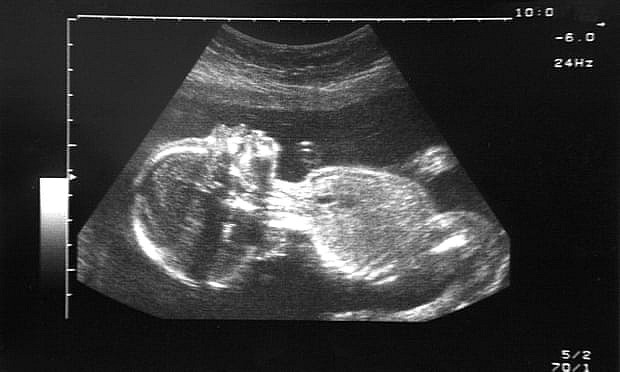

Tổn thương trong thai kì theo đứa trẻ suốt đời

Joan Casey - trợ lý khoa học sức khỏe môi trường tại Đại học Columbia cho biết: “Mức độ ô nhiễm không khí nơi nghiên cứu này diễn ra thấp đến mức chúng ta thường không thấy kết quả bất lợi về sức khỏe, hoặc không nhiều. Nhưng có thể có một ngưỡng khiến vấn đề trở nên nghiêm trọng. Tôi rất muốn thấy điều này được thực hiện ở những nơi như Bắc Kinh hoặc Ấn Độ - nơi tình trạng ô nhiễm đang tăng cao, chúng ta có thể mong đợi sẽ nhìn thấy mức độ ảnh hưởng rõ rệt hơn, chính xác hơn”.

Ở Hoa Kỳ, trung bình mức độ ô nhiễm không khí đã giảm trong những thập kỷ gần đây, điều này có nghĩa là những phát hiện của nghiên cứu có thể không cung cấp câu trả lời chính xác về tỷ lệ mắc bệnh hen suyễn ở trẻ em và chẩn đoán chứng tự kỷ. Noel Mueller - Giáo sư dịch tễ học tại trường Johns Hopkins Bloomberg, người nghiên cứu tác động của phơi nhiễm vật chất hạt đối với trẻ em cho biết ông hy vọng sẽ áp dụng những phát hiện này vào công việc của mình với các đoàn hệ lớn ở khu vực Boston. Năm 2018, Mueller đã đồng công bố một nghiên cứu cho thấy những đứa trẻ được sinh ra bởi những bà mẹ tiếp xúc với chất hạt cao có nhiều khả năng bị huyết áp cao trong những năm đầu đời.

“Chúng tôi đã có một số giả thuyết về việc phơi nhiễm có thể ảnh hưởng đến thai nhi như thế nào, đó là vấn đề hạt carbon có thể vượt qua hàng rào nhau thai và tích tụ lại. Nghiên cứu này cung cấp bằng chứng về nguyên tắc rằng việc người mẹ tiếp xúc với ô nhiễm không khí khi mang thai có thể ảnh hưởng đến không chỉ người mẹ mà còn cả thai nhi” - Mueller nói.

Giáo sư Tim Nawrot của Đại học Hasselt chia sẻ: “Sẽ rất nguy hiểm nếu thai nhi bị ảnh hưởng bởi ô nhiễm không khí. Những tổn thương xảy ra trong thai kỳ có thể để lại hậu quả suốt đời cho một đứa trẻ. Đây là thời kỳ mong manh, dễ bị ảnh hưởng nhất trong cuộc đời của mỗi người, khi tất cả các cơ quan nội tạng đang được hình thành và phát triển. Để bảo vệ các thế hệ tương lai, chúng ta cần phải giảm thiểu ô nhiễm”.

Theo ông, các nước cần nang cao trách nhiệm cắt giảm ô nhiễm không khí, tuy nhiên, trong khi hành động chưa thực sự ráo riết, mọi người và đặc biệt là các thai phụ, cần chủ động tránh những nơi đông đúc, nhiều khói bụi, giờ giao thông cao điểm… khi có thể.

Giáo sư Grigg, một thành viên nhóm nghiên cứu, cho biết: “Chúng tôi tìm thấy các hạt ô nhiễm trong cơ thể của mọi phụ nữ. Như vậy, mỗi ngày chúng ta đều bị bủa vây bởi những hạt này. Các thai phụ là đối tượng cần lưu ý bảo vệ sức khoẻ nhất. Đây chính là dấu hiệu báo động, cho thấy chúng ta cần hành động ngay để giảm thiểu ô nhiễm không khí”.